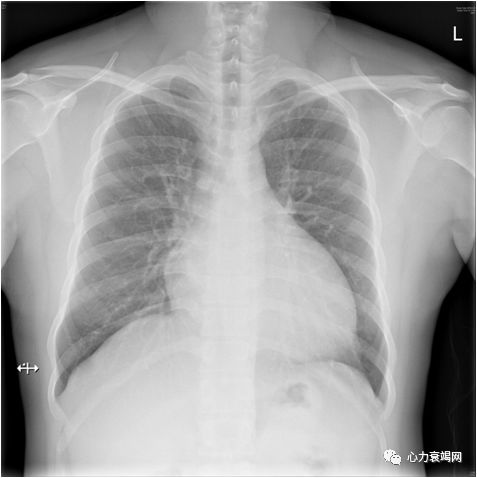

胸部X-ray

两肺淤血

全心增大

心胸比0.55